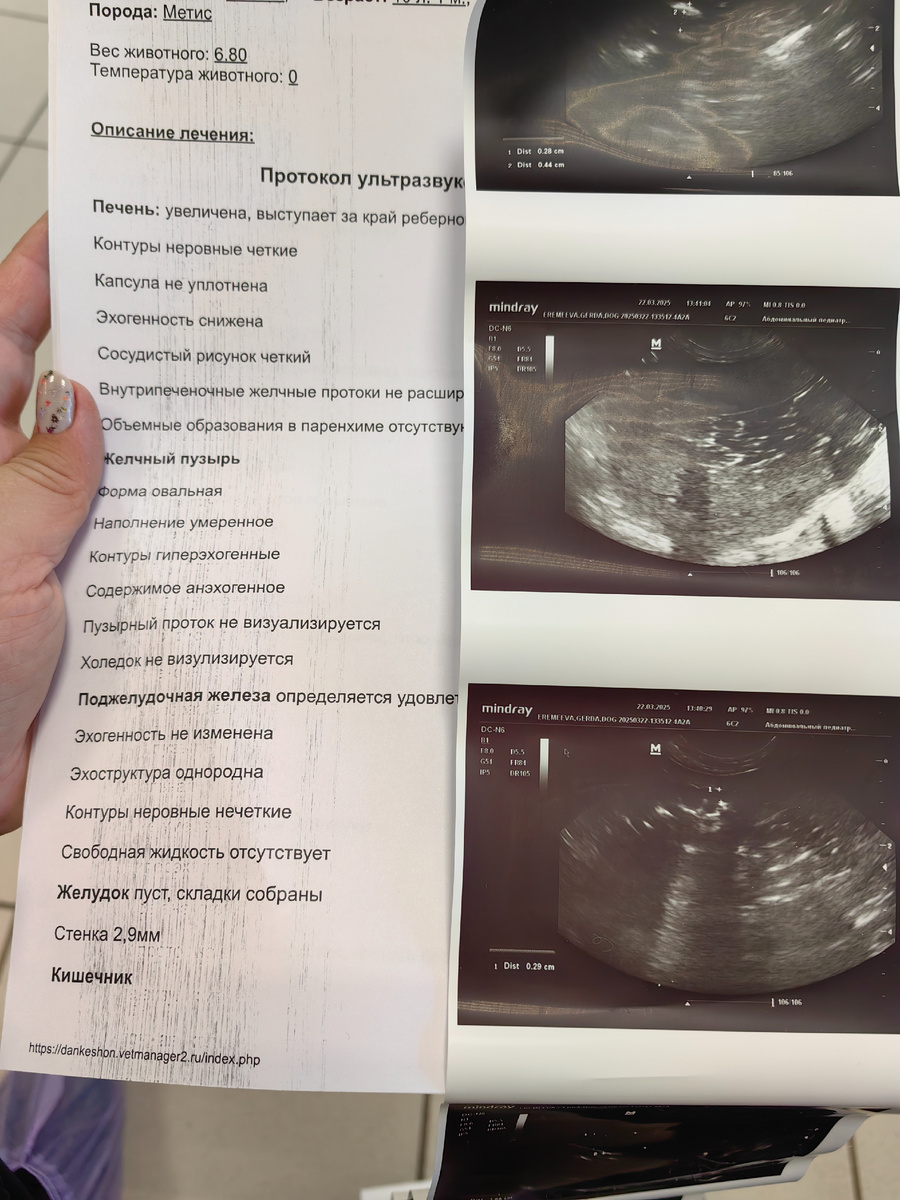

С утра пошли с собачкой на уколы, мы сдали вчера еще анализы и записаны были на УЗИ на вторник. Живот у Геры не проходит и аппетита нет. В клинику она совсем идти не хотела, пришлось нести часть дороги на руках, пожалела, что не взяла коляску. Когда мы пришли, нас уже ждали в стационаре. Пришли результаты крови и печеночные показатели плохие. Поставили ей капельницу, посадили в бокс, она пыталась освободить лапку, надели воротник. Оставили ее там до 15-00 и сказали подойти, сделают УЗИ. Дома я не находила себе места, заодно перебрала на лоджии бардак и кучу мусора выкинула. Пришла за Герой к трем, а ей уже все сделали. В итоге назначили поддерживающую терапию, капельницы пять дней. Уколы, еще вечером пойдем на укольчик сходим. В мае нам на УЗИ сказали, что печень плохая и выписали курс, мы его пропили. Живот у Геры так и болит, стул жидкий, аппетита нет. Хорошо, что коляску взяла, из-за лапки с катетером наша нежная собачка еле шла. А еще у нас вечером вчера упал замертво в кле

Когда мы пришли, нас уже ждали в стационаре. Пришли результаты крови и печеночные показатели плохие.

Оставили ее там до 15-00 и сказали подойти, сделают УЗИ.

В итоге назначили поддерживающую терапию, капельницы пять дней. Уколы, еще вечером пойдем на укольчик сходим.

В мае нам на УЗИ сказали, что печень плохая и выписали курс, мы его пропили.

Живот у Геры так и болит, стул жидкий, аппетита нет.